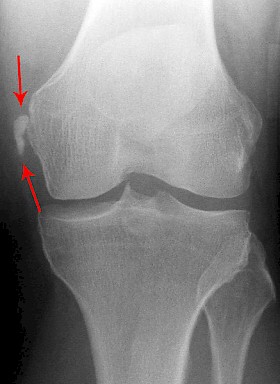

Die Fabella ist ein zusätzlicher kleiner Knochen, der als Zufallsbefund bei Röntgenaufnahmen häufig in der Kniekehle nachweisbar ist.

Als Fabella (lat. Verkleinerungsform von lat. faba „Bohne“), auch Os sesamoideum musculi gastrocnemii oder Vesalisches Sesambein (nach Andreas Vesalius), bezeichnet man ein Sesambein (ein in eine Sehne eingelagertes Knöchelchen) in der Ursprungssehne des Musculus gastrocnemius. Es befindet sich an der Hinterseite des Kniegelenks, unmittelbar oberhalb des Kondylus des Femurs.

In der Betrachtung von seitlichen Röntgenaufnahmen des Kniegelenkes steht oft die Frage eines traumatisch abgesprengten Knochenfragmentes im Raum. Die Fabella weist jedoch, im Gegensatz zu einem Fragment, eine allseitige Kortikalis ohne Kontinuitätsunterbrechung auf. Weiterhin differentialdiagnostisch miteinzubeziehen ist in diesem Zusammenhang der Stieda-Pellegrini-Köhler-Schatten.

Die Fabella kommt bei ca 10 % aller Menschen im Ursprung des seitlichen Kopfs des Musculus gastrocnemius vor, bei Frauen dabei etwas häufiger als bei Männern. Seltener finden sich 2 oder 3 solcher Knöchelchen (Fabella bi- bzw. tripartita). Bei Raubtieren (z. B. Hunde, Katzen) treten Fabellen stets beidseitig, also in den Sehnen beider Köpfe des Musculus gastrocnemius, auf.